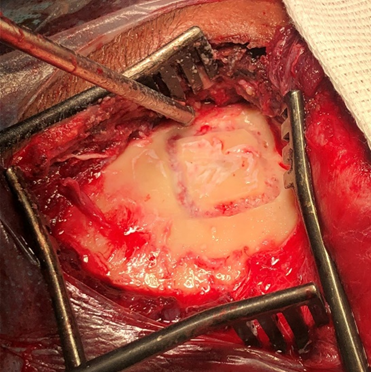

Figure 4 Surgical procedure.

Craniotomy for access to the middle fossa in the supra-auricular region of the right ear.